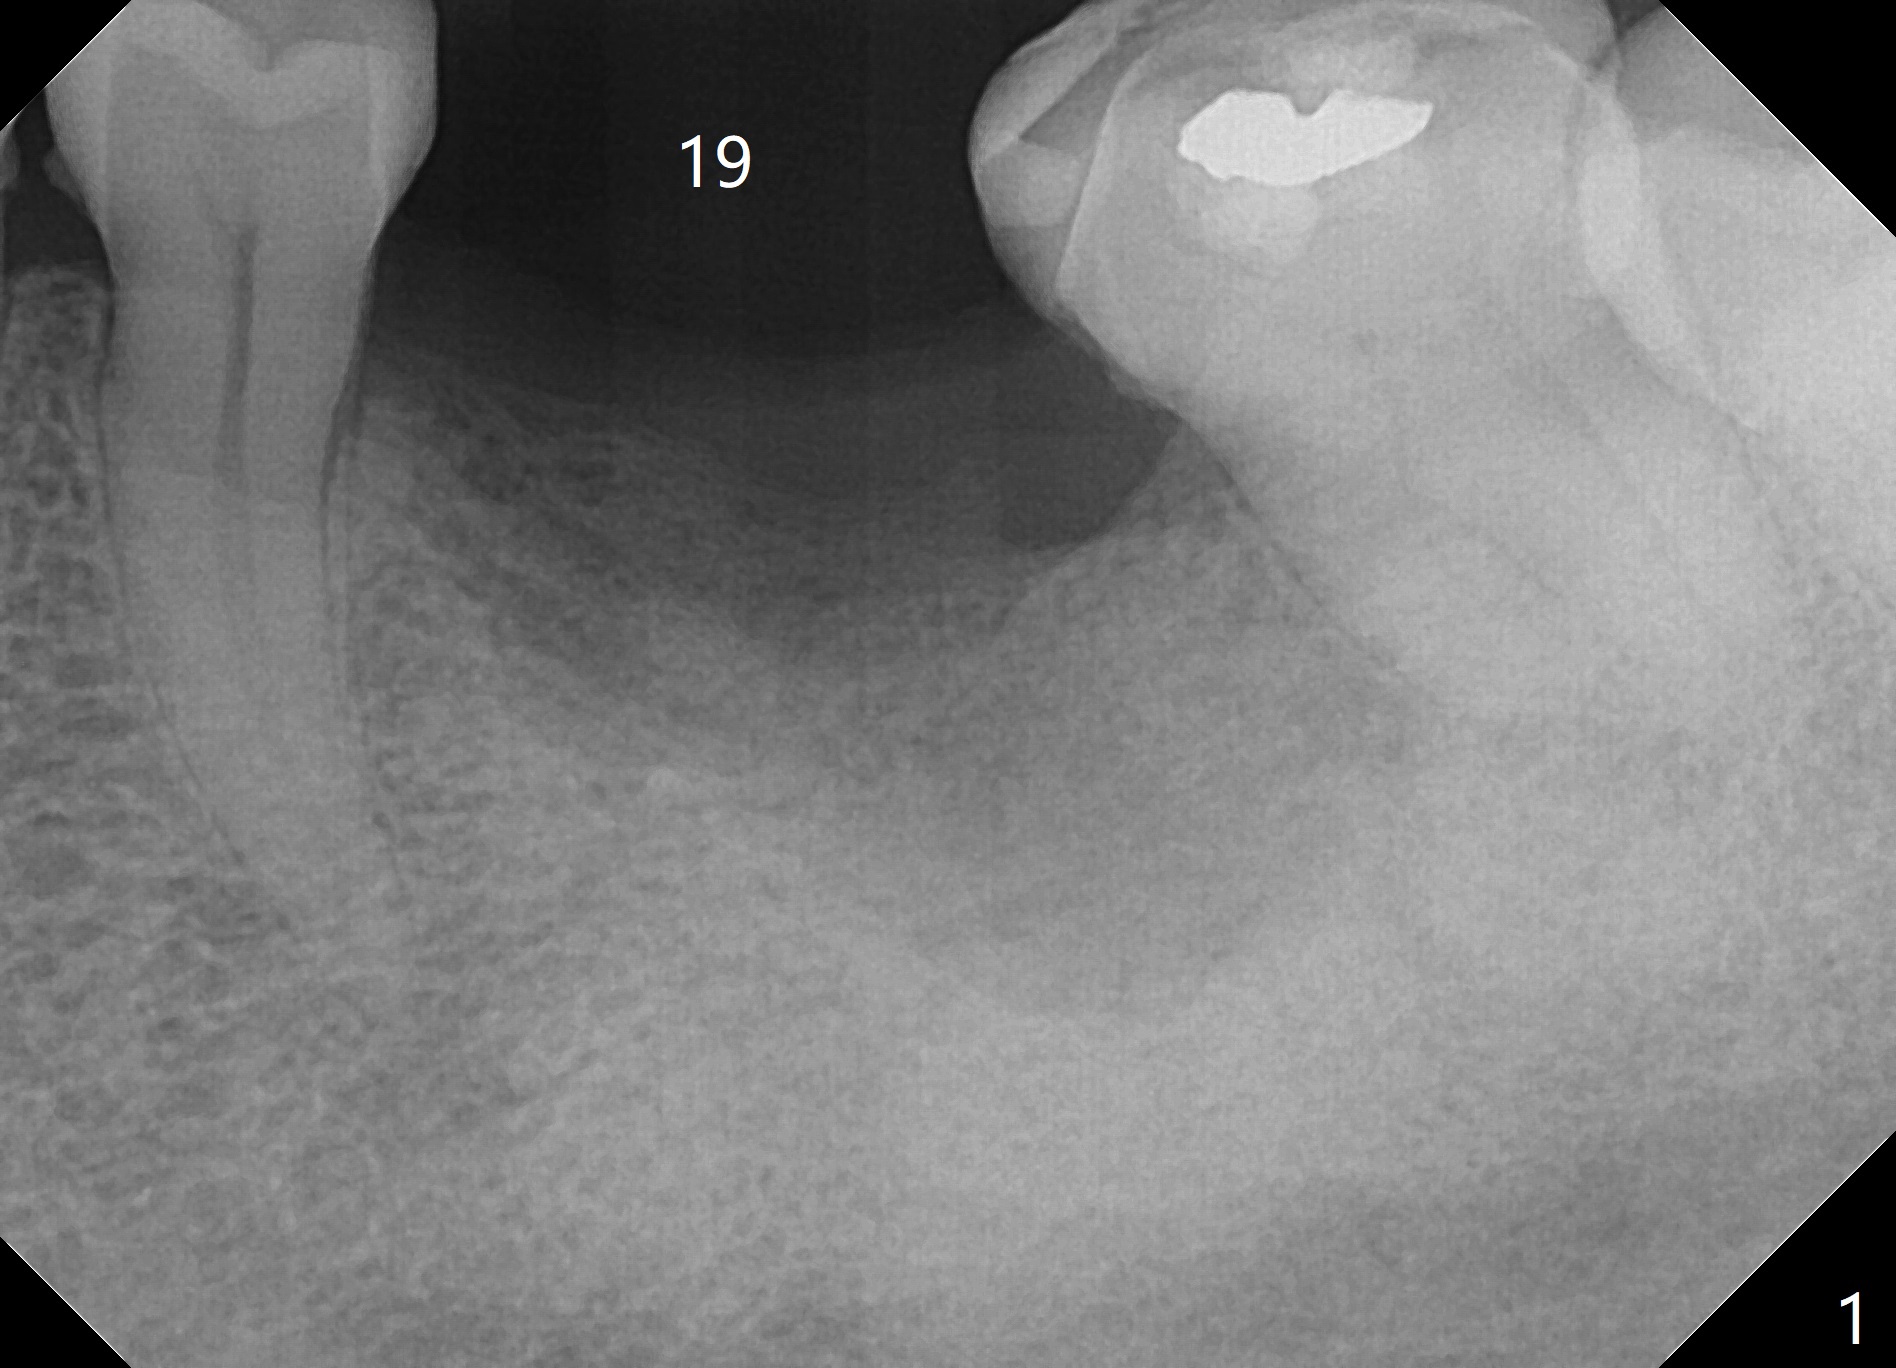

A 59-year-old woman had the tooth #19 with apparently residual roots extracted in her home country ~ 6 months ago (Fig.1). There seems to be severe bone plate resorption, with the buccal crest (Fig.2 red dashed line) 7-8 mm lower than the lingual one (pink dashed line). Following flap reflection, an osteotomy will be established between the crests (Fig.2 white circle). A 4 or 4.5x10 mm implant with high stability (Fig.4 green outline) will be placed ~ 4 mm (yellow line) below the lingual crest and ~ 4 mm above the buccal one. The implant is going to have > 5 mm in the native bone (pink). It may have ~ 2 mm (red line) clearance from the Inferior Alveolar Canal. Since the implant is most likely placed lingually, prepare the Planning Kit and an angled abutment. Vanilla graft will be placed buccally, followed by PRF membranes. One of the latter has a hole for the abutment to penetrate.